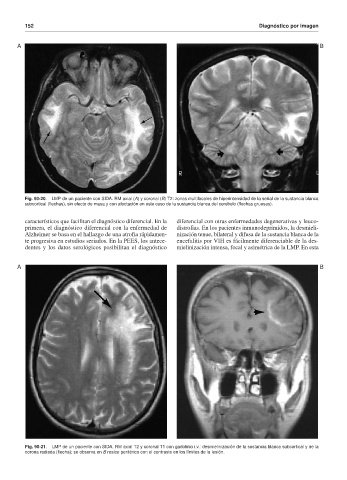

Fig. 90-20. LMP de un paciente con SIDA. RM axial (A) y coronal (B) T2: zonas multifocales de hiperintensidad de la señal de la sustancia blanca

subcortical (flechas), sin efecto de masa y con afectación en este caso de la sustancia blanca del cerebelo (flechas gruesas).

Fig. 90-21. LMP de un paciente con SIDA. RM axial T2 y coronal T1 con gadolinio i.v.: desmielinización de la sustancia blanca subcortical y de la

corona radiada (flecha); se observa en B realce periférico con el contraste en los límites de la lesión.